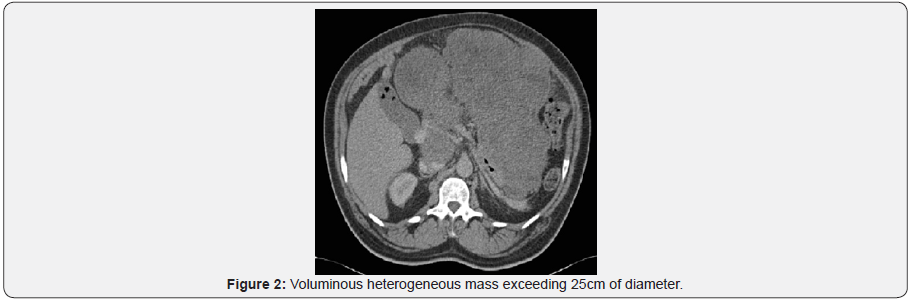

A contrast-enhanced thoraco-andominal CT-scan showed a voluminous abdominal mass measuring 25 x 20cm located in the stomach as well as two liver lesions. No pulmonary lesions were found. After a multidisciplinary discussion, we decided to proceed to a surgical biopsy of the gastric mass in order to identify the etiology. The anatomopathological analysis revealed a Gastrointestinal Stromal Tumor, probably of gastric origin. We decided to start a treatment with Imatinib (Glivec) 400mg [5]. The medical treatment with Imatinib worked well at first but a further increase in volume of the mass, but not the metastases, was discovered after four years. After a new multidisciplinary discussion, given the resectability of the lesion, it was decided to perform a surgical “en bloc” resection of the tumor [6].

If surgery is the standard procedure for all GIST of small intestine or rectum it is not the case for gastric GIST. The treatment strategy in these cases is affected by several factors: the size of the tumor, its location, its adhesions to nearby structures and presence or absence of metastasis [1,9] (Figure 1-7).